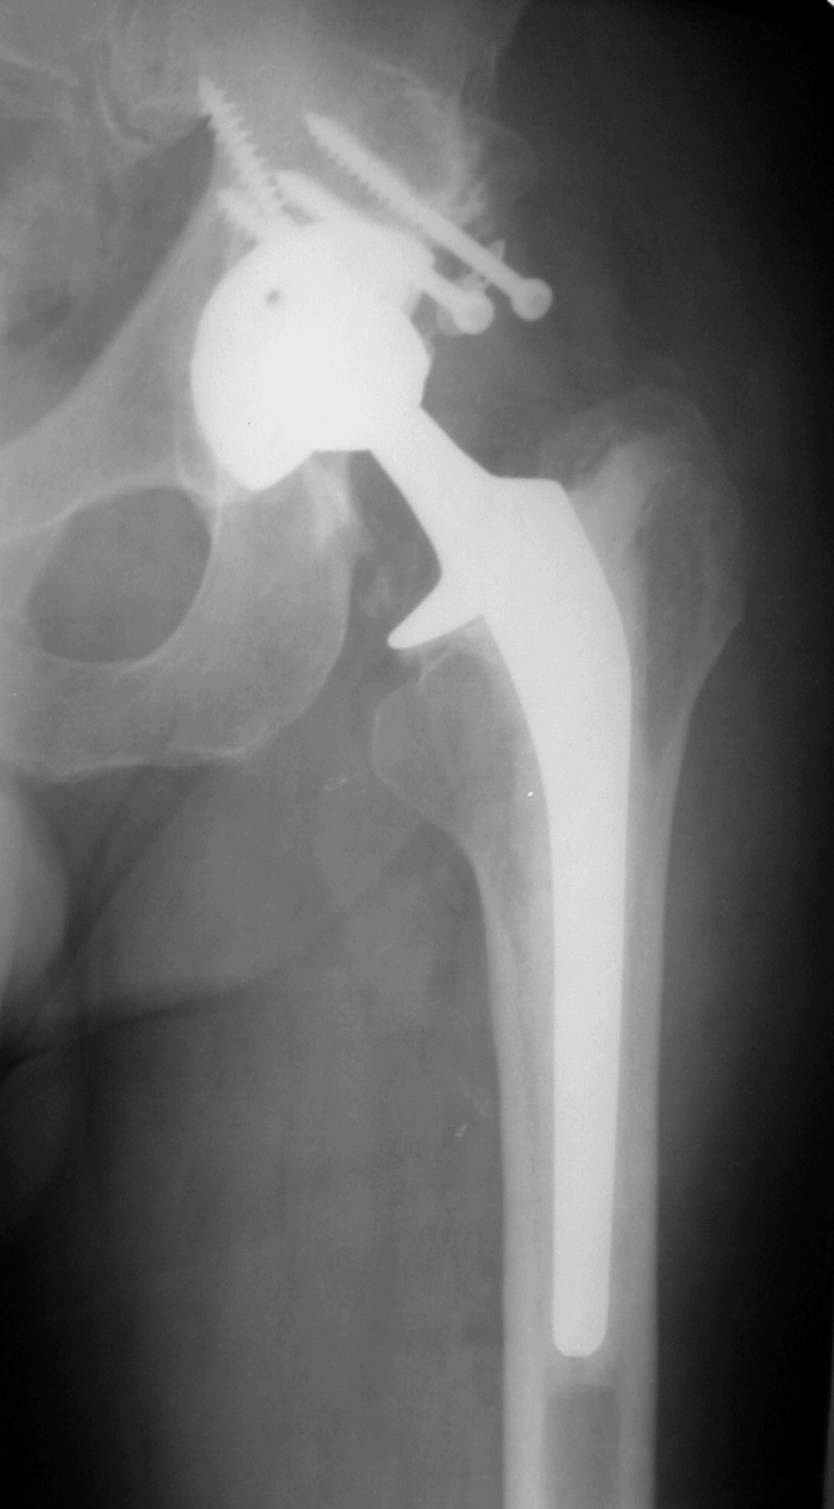

В институте совместно с фирмой Зиммер достаточно регулярно (практически ежемесячно) проводятся 2-х недельные циклы по различным вопросам эндопротезирования. Если есть возможность и желание, мы готовы поделиться с Вами нашим опытом, тем более есть что показать и что обсудить - в настоящее время ежедневно выполняется от 6 до 10 эндопротезирований коленного и тазобедренного сустава. В качестве примеров хочу показать 2 наблюдения, через 1 год и 5 лет после операции

С уважением, Р.Тихилов

5 лет